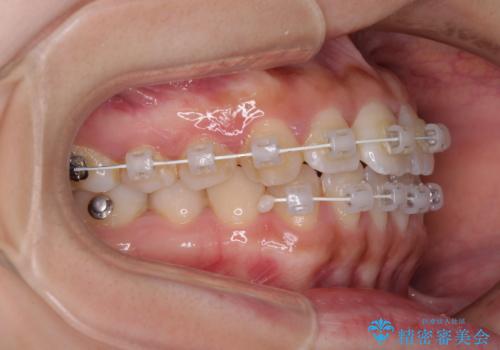

- 矯正装置

- 審美装置

上顎からワイヤー矯正を開始し、終了間際から下顎前歯の叢生解消するよう計画しました。

部分矯正でしたが、咬み合わせに違和感が出ることなく気になる部分を改善させることができました。